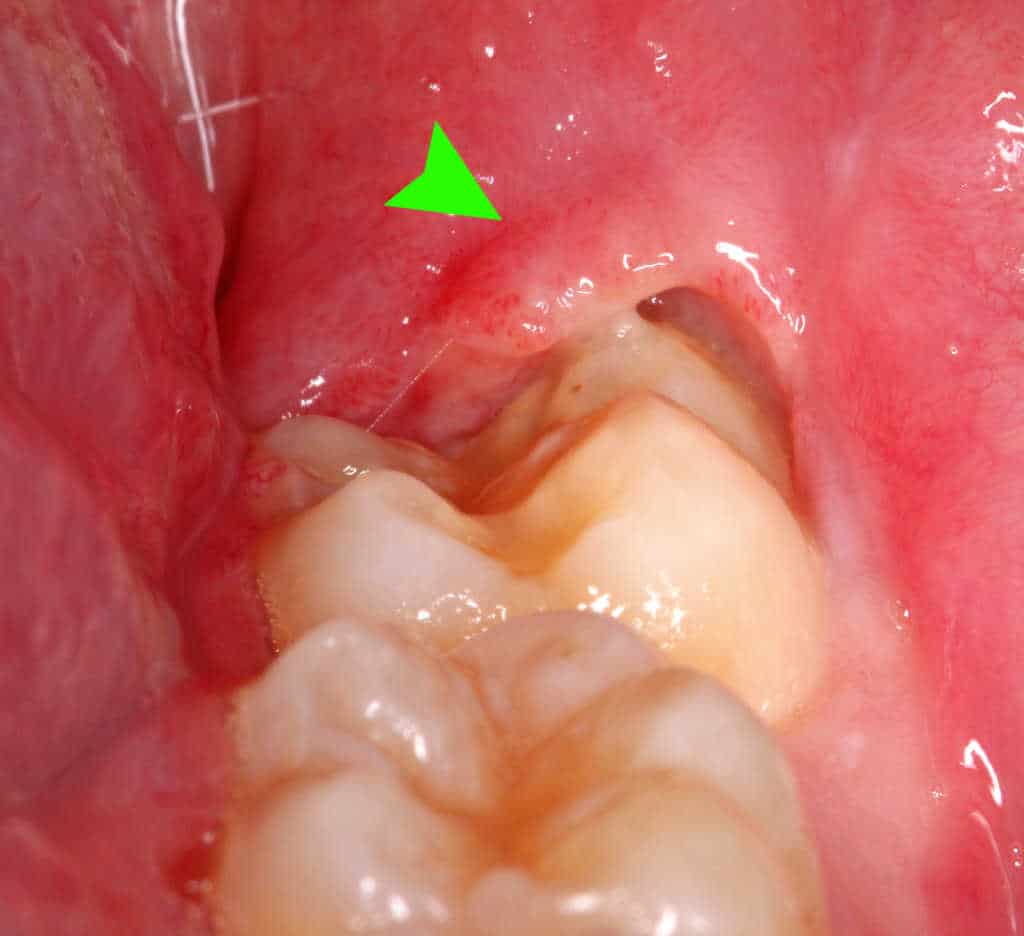

1. 치관주위염의 예방과 치료

치관주위염 (출처 : 위키피디아)

치관주위염은 20대 이후 사랑니 발치가 이루어지는가장 흔한 원인입니다. 사랑니가 잇몸을 뚫고 일부만 맹출 되는 경우 사랑니의 머리 부위는 치은판개(operculum)라는 잇몸의 일부로 덮여있게 됩니다. 부분 맹출된 사랑니의 관리가 잘 이루어지지 않을 경우 치아와 치은판개 사이 공간으로 음식물이나 이물질이 끼이게 되어, 세균이 성장하는 배지가 될 수 있습니다.

면역력이 약화된 경우 붓고 아프게 되며, 항생제와 소염진통제를 통해 일시적으로 증상을 완화시킬 수는 있지만, 재발을 막기 위해서는 연관된 사랑니를 발치하는 것이 좋습니다.